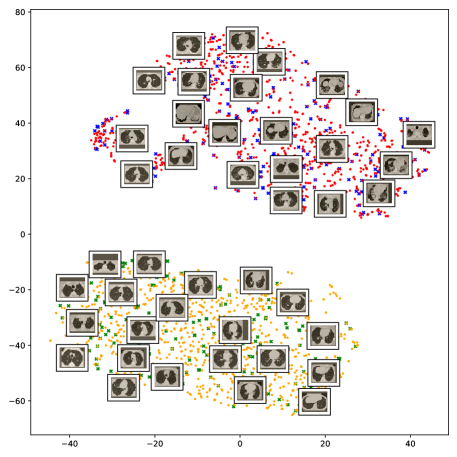

In order to provide better explainability of the deep models and making them more transparent we apply two visualization techniques. The first approach is the t-distributed Stochastic Neighboring Embedding (t-SNE) [13], which is a dimensionality reduction and visualization technique for visualizing clusters of instances in a high-dimensional space. The obtained visualizations of the t-SNE embeddings show well-separated clusters representing CT images for COVID-19 and Non-COVID-19 cases. The second approach is the Gradient-weighted Class Activation Mapping (Grad-CAM) [14], which is a visualization technique for CNN-based models. It provides high-resolution and class-discriminative visualizations that localize the important image regions considered for the model prediction. The Grad-CAM visualizations show how accurately our models localize the COVID-19 associated regions. Overall, this paper exhibits the following contributions:

5.5 Visual Explanations

This subsection provides visual explanations to make our models more transparent. We start with a 2D projection of the learned features using t-SNE [13], and then present the localization maps for highlighting the COVID-19 associated regions using Grad-CAM [14].

5.5.1 The t-SNE visualization

To understand how the deep neural networks represent the CT images in the high-dimensional feature space we apply the t-SNE algorithm to visualize these features. For each image in the SARS-CoV-2 dataset we first extract the 2048-dimensional feature vector from the penultimate layer of the Inception V3 model. Next, we apply t-SNE to map the features on to 2D space and then visualize the embeddings of training and test representations. Figure 11 clearly shows two well-separated clusters of the CT images of COVID-19 and Non-COVID-19. This indicates that the distribution of training and test features are quite similar to each other, which indicates good generalization capabilities of our model. The clear and wide margin between the two classes shows how nicely the CT images are separated in feature space.

We also repeat the same procedure for the COVID19-CT dataset. The feature vectors are extracted from the penultimate layer of the DenseNet169 model. The length of the feature vectors is 1664 dimensions. We again apply t-SNE to map the features on to 2D space to explore and visualize them. Figure 12 shows two clusters representing CT images for the COVID-19 and Non-COVID-19 classes. Even though the classes are fairly distinguishable with a clear decision boundary, however, we can see that some CT images are misclassified, and more specifically the Non-COVID-19 CT images from the test set.